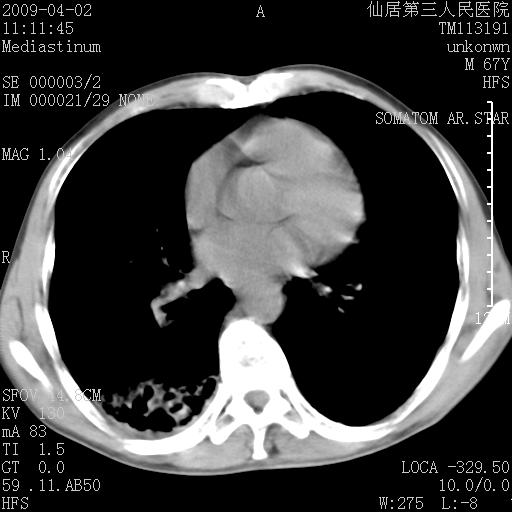

患者老年男性,乏力畏寒来诊,摄胸片示右下肺感染性病变,抗炎两周后复查胸片,无好转有进展。

后做ct平扫表现如下:

考虑右肺炎症可能性大,不除外细支气管肺泡癌

是否还要考虑肺间质纤维化,建议hrct扫描。

考虑间质性肺炎。

病灶呈蜂窝征,纵隔多个淋巴结肿大;肺泡癌需考虑

右肺下叶背段干酪性肺炎。请痰检[emb28]

我认为普通的感染应该可以除外,间质性肺炎可能性较大,但如何解释纵膈的淋巴结肿大呢

考虑双肺间质性改变(间质纤维化?)伴右肺下叶感染。